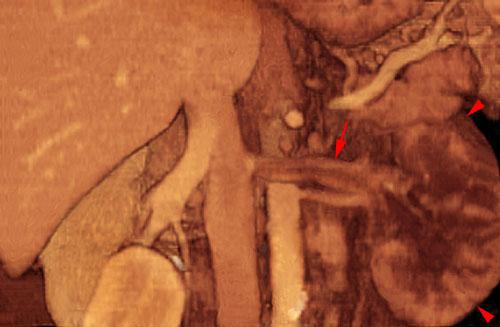

Síndrome del cascanueces retroaórtico